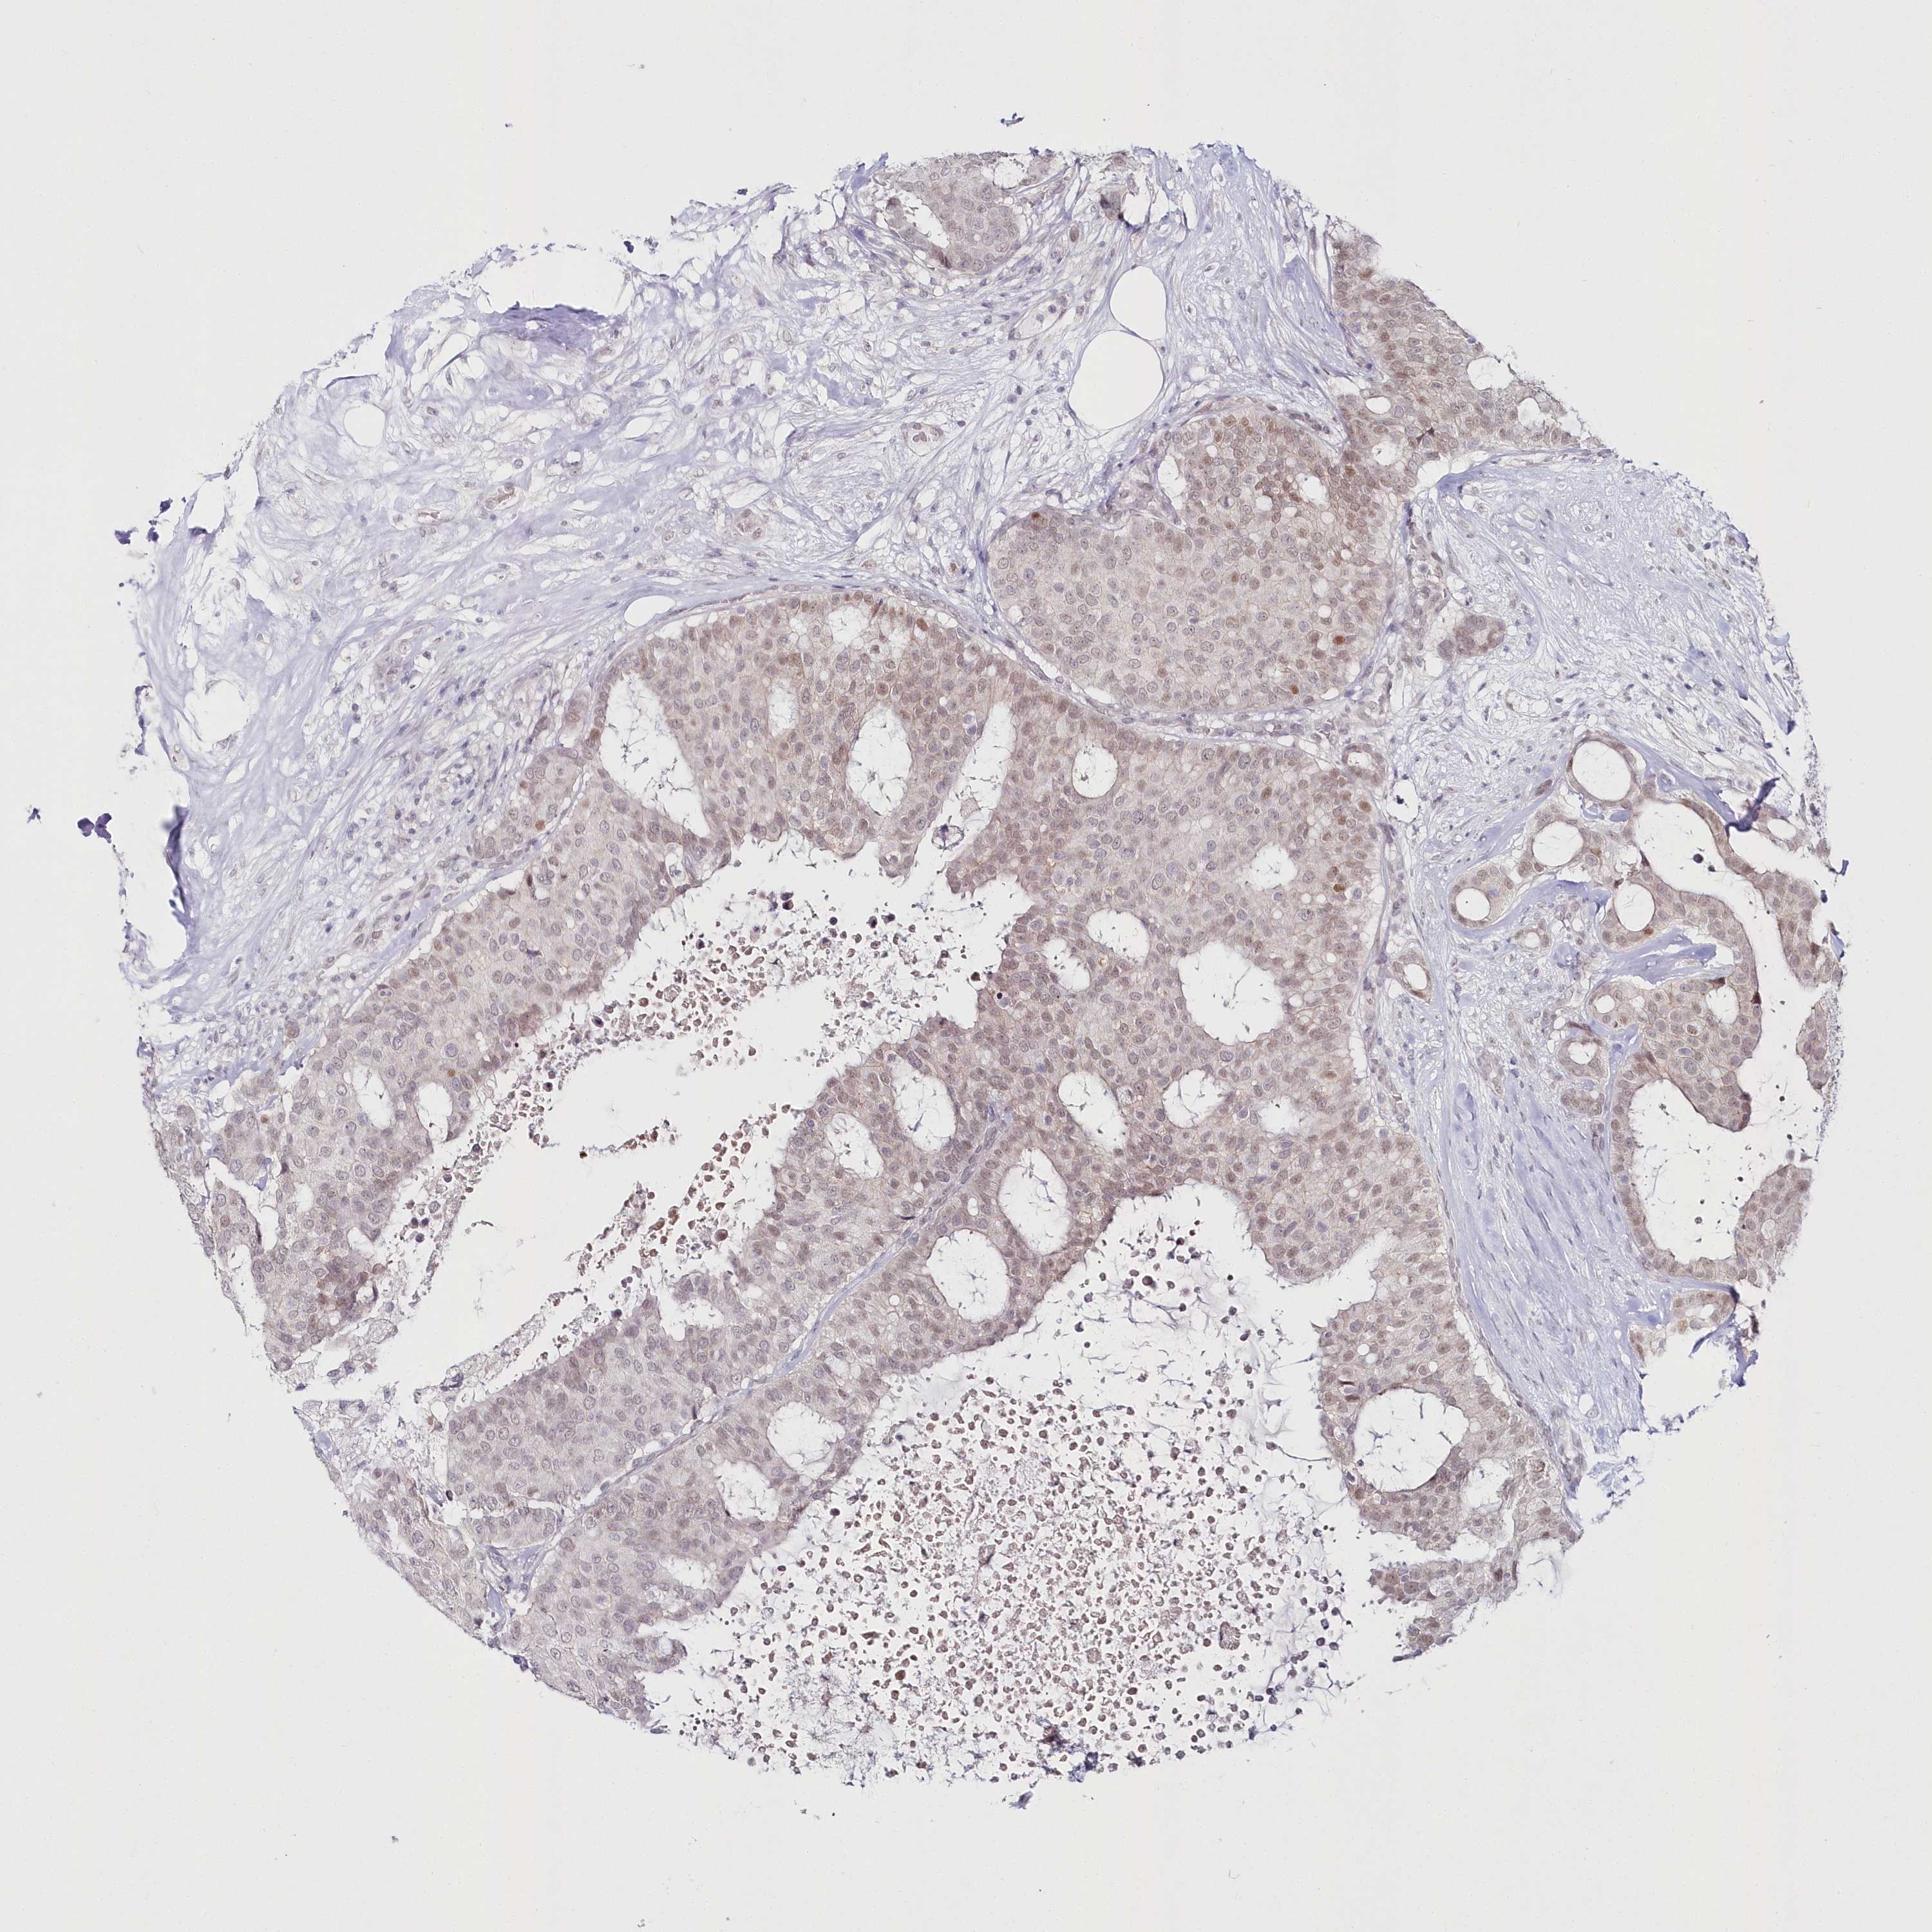

CANCER BREAST CANCER Show tissue menu

BRCA TCGA BRCA VALIDATION PROTEIN EXPRESSION